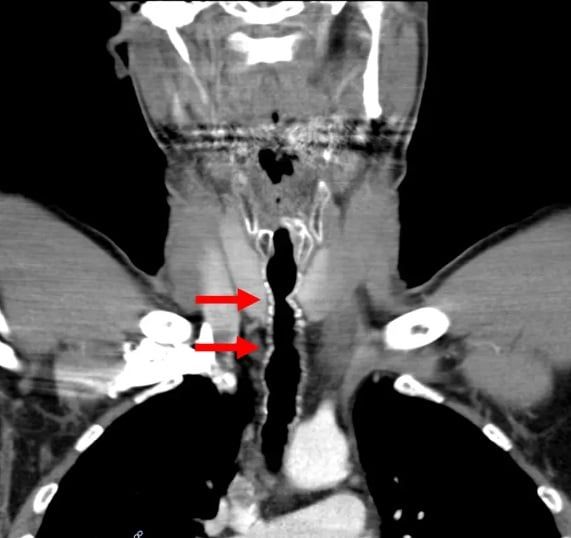

نمو الشعر في حلق الرجل American Journal of Case Reports

وبعد إخضاعه للفحوصات، اكتشف الأطباء التهابًا ونمو شعر في حلقه، لتتم إزالة الشعر ومعالجته بالمضادات الحيوية.

الشعر في حلق الرجل American Journal of Case Reports